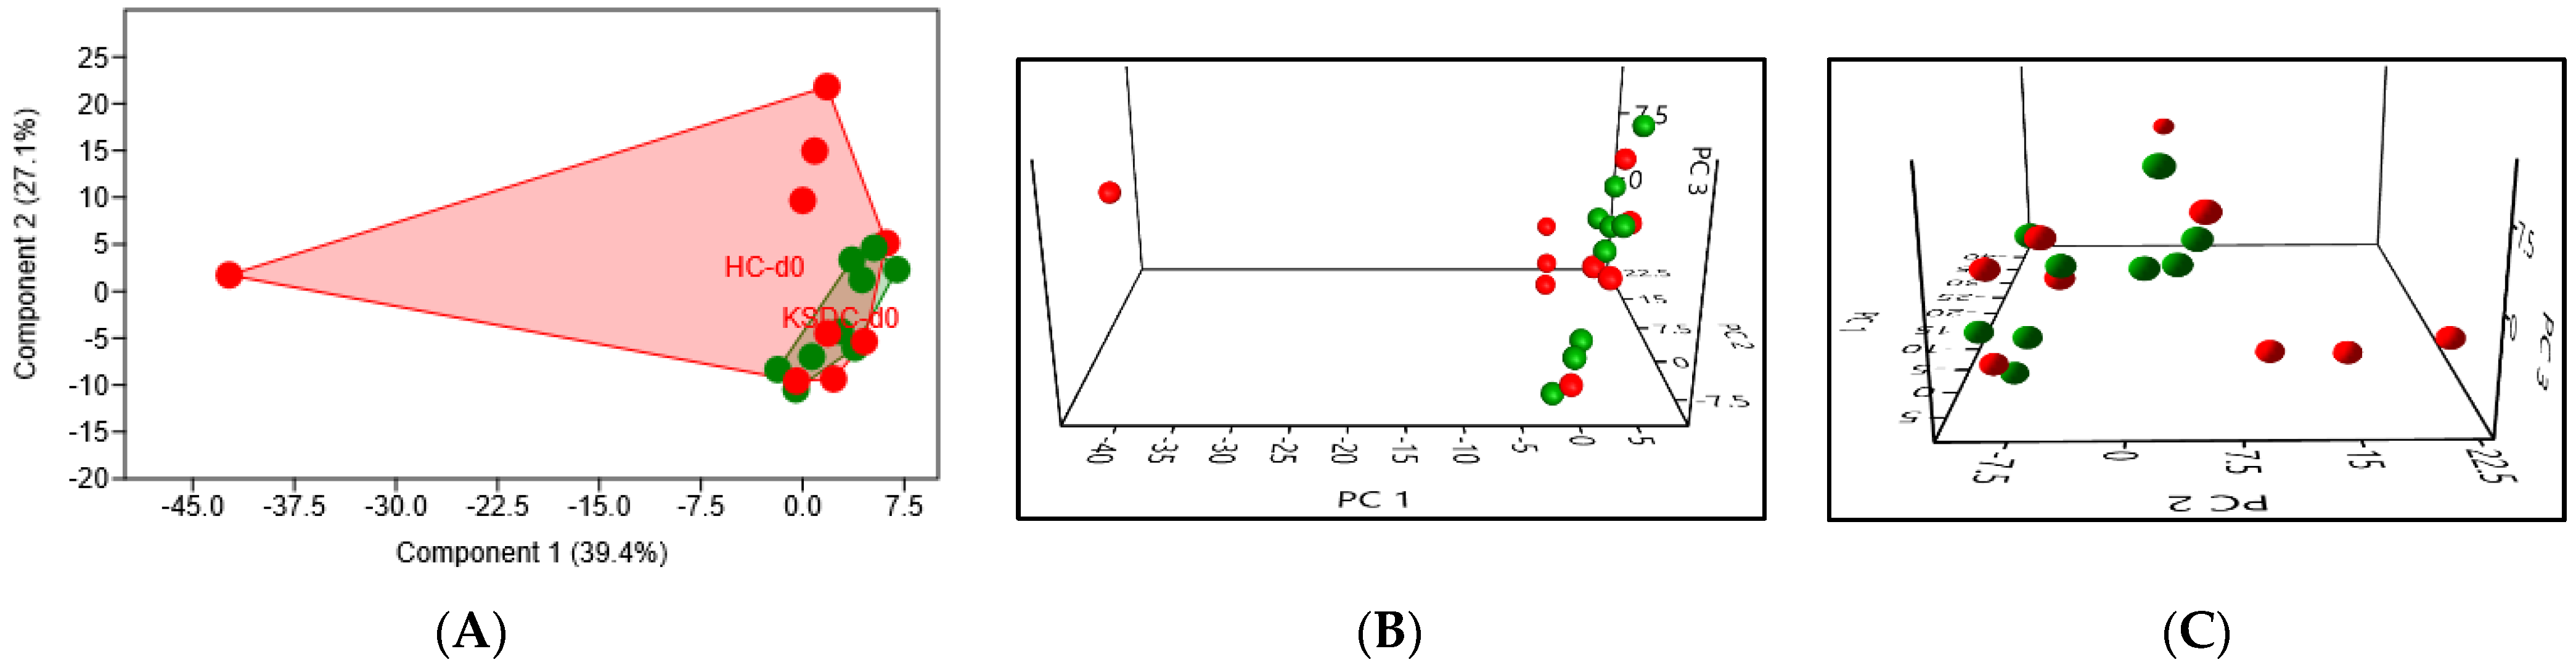

3.2.2. Beta Diversity

Taxonomic Analysis of the Intestinal Microbiota Composition at D0 in the Two Cat Populations

Biodiversity of the Fecal Microbiota in the Two Cat Populations